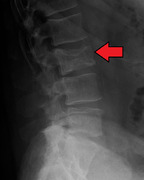

Illustration showing the most common site of bone lesions in vertebrae

Bone pain affects almost 70% of people with multiple myeloma and is the one of the most common symptoms.[2]:653[16] Myeloma bone pain usually involves the spine and ribs, and worsens with activity. Persistent, localized pain may indicate a pathological bone fracture. Involvement of the vertebrae may lead to spinal cord compression or kyphosis. Myeloma bone disease is due to the overexpression of receptor activator for nuclear factor κ B ligand (RANKL) by bone marrow stroma. RANKL activates osteoclasts, which resorb bone. The resultant bone lesions are lytic (cause breakdown) in nature, and are best seen in plain radiographs, which may show "punched-out" resorptive lesions (including the "raindrop" appearance of the skull on radiography). The breakdown of bone also leads to the release of calcium ions into the blood, leading to hypercalcemia and its associated symptoms.